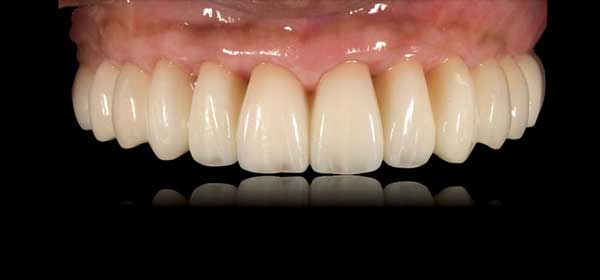

3. 魅了する上部構造

患者様それぞれに最適な上部構造をお選び頂けます。 オールオン4クリニック では、画一的な上部構造を提供致しません。フレーム、歯肉、歯、それぞれ、多彩なバリエーションをご用意しております。